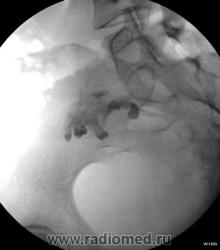

Наблюдение Виктора Григорьевича. ТЕРАТОМА или "Зубы в малом тазу".

Чкстно говоря - я тоже такое чудо увидел первый раз за 25 лет работы в радиологии...сначала была обзорная рентгеноскопия брюшной полости, потом - ирригоскопия, наблюдалось легкое оттеснение сигмовидной, прямой и слепой кишки, при случае постараюсь и эти снимки предоставить.

Это не круто, это навевает на мысль - на возможность появления новой профессии (в плане доступа) - "проктолог - стоматолог", зубы-то четко видны, а мы-то, знаем как болят зубы? А "там-то", их, пускай, и "заблудшие", но родственники (по зародышевым листкам).